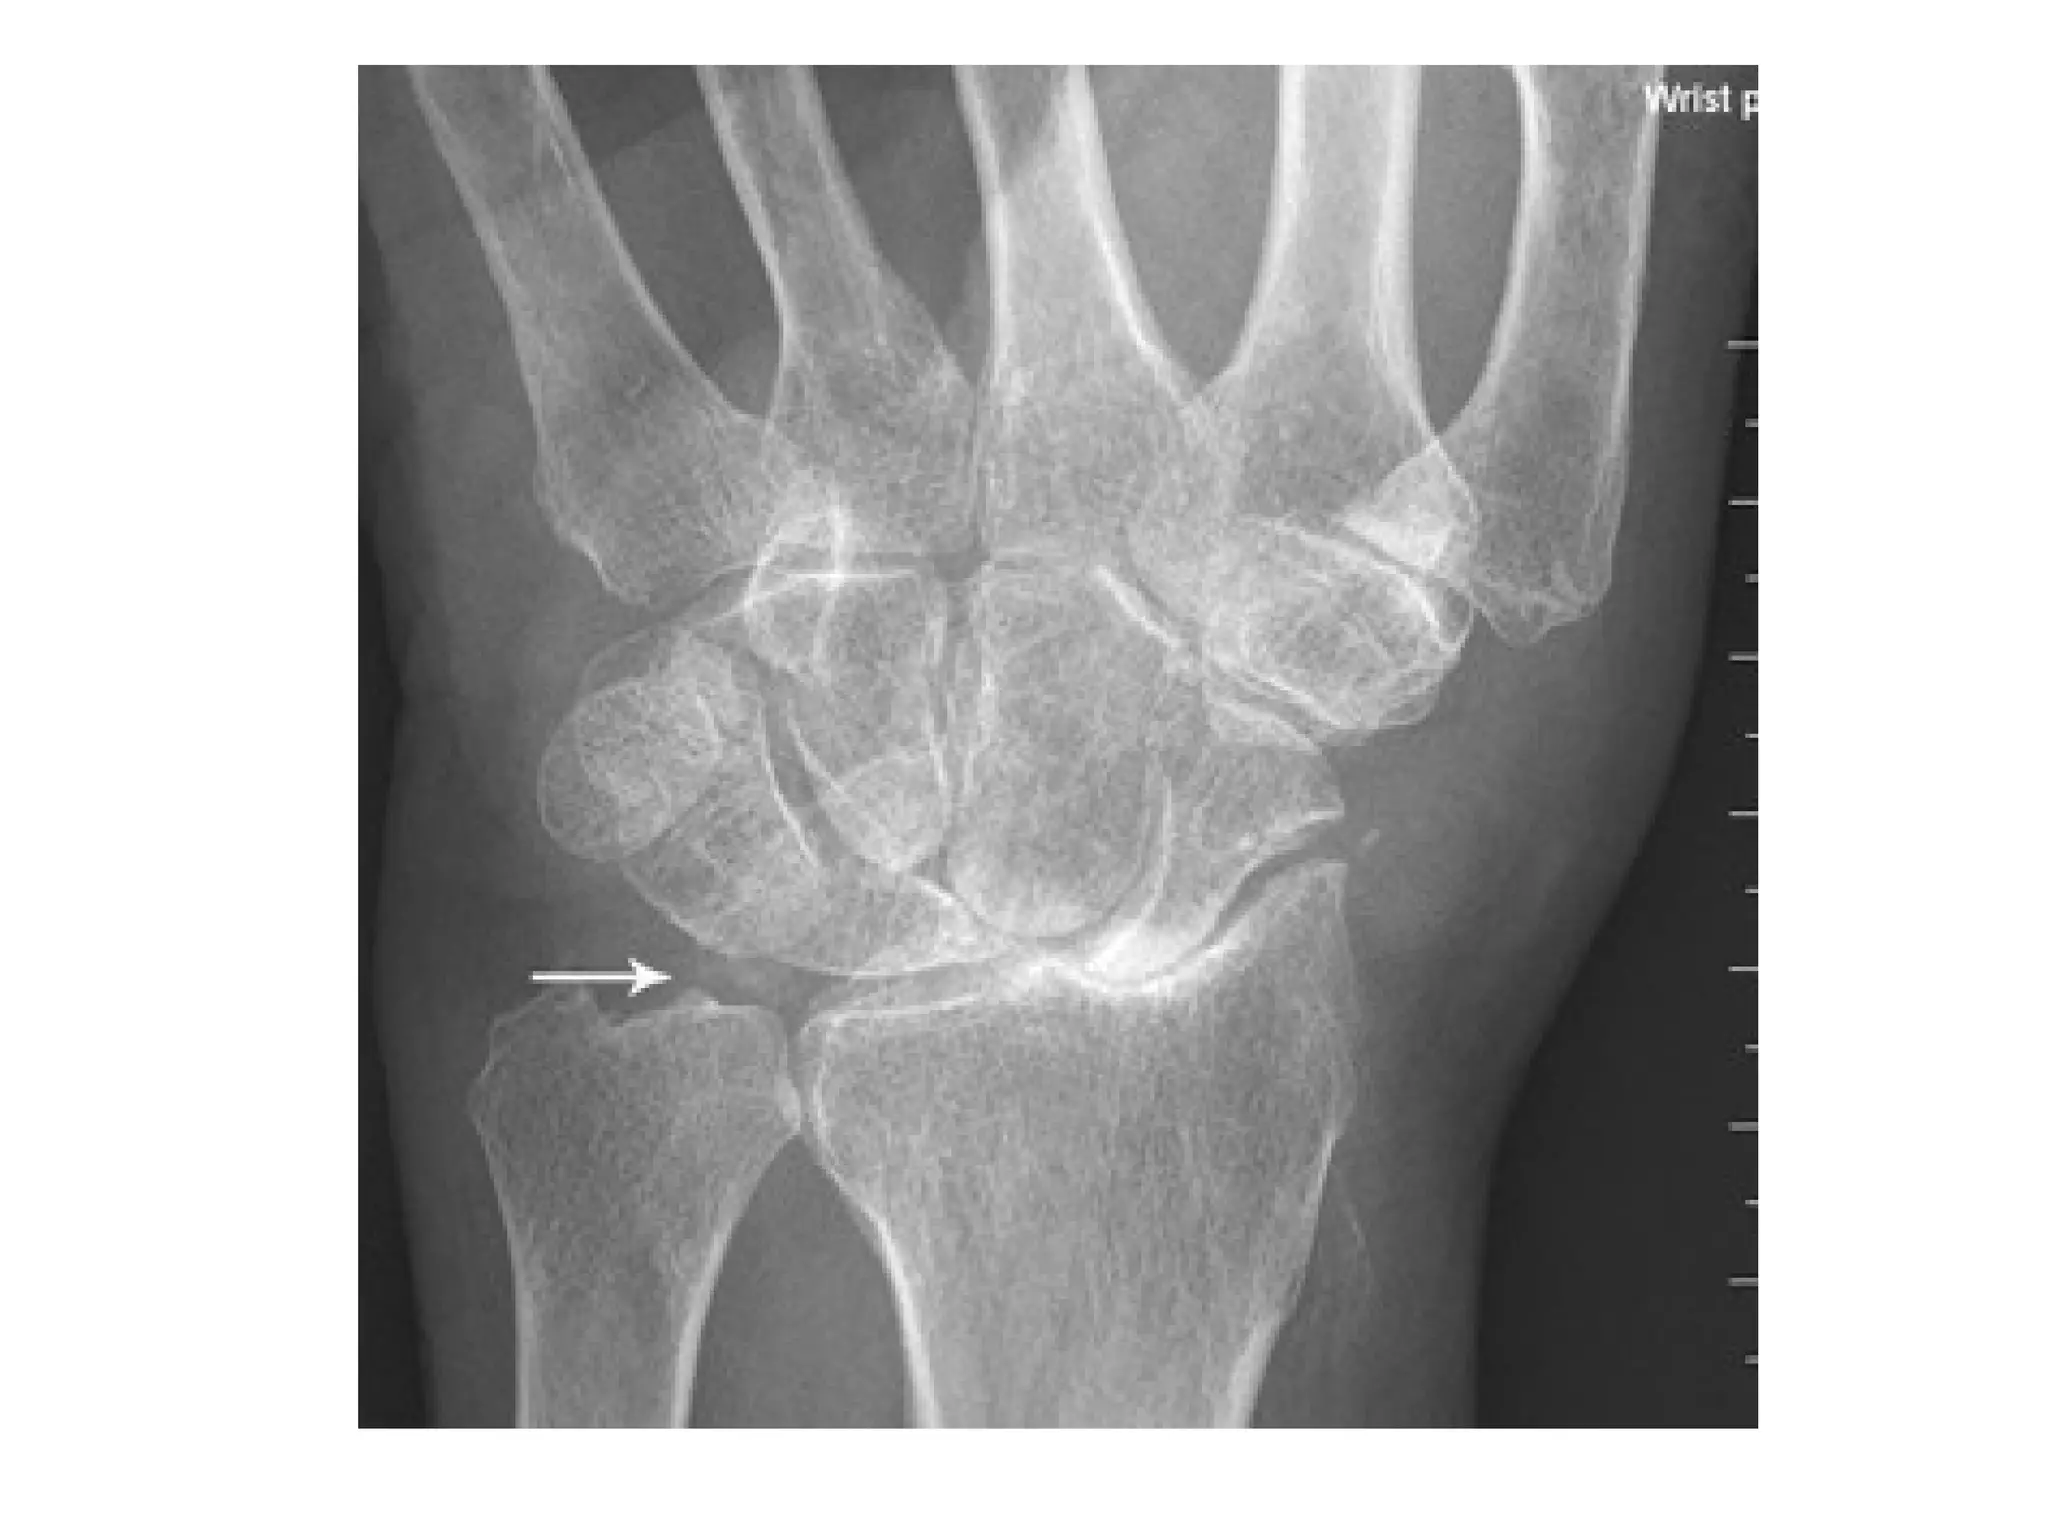

Tophaceous gouty arthritis , extensive bony erosions are noted

throughout the carpal bones , urate depositions may be present in

the periarticular areas

Scapholunate advanced collapse (SLAC) wrist secondary to CPPD , PA view of the wrist

shows widening of the scapholunate distance (arrowhead) with proximal migration of

the capitate and calcification of hyaline cartilage , triangular fibrocartilage (arrow) and

interosseous lunotriquetral ligament , Subchondral cysts also are seen in the carpal

bones and at the base of the fifth metacarpal

(SLAC) , there is chondrocalcinosis in the triangular fibrocartilage of the

ulna (white arrow) , there is narrowing of the radio-carpal joint and

proximal migration of the capitate into the widened space between

the scaphoid and the lunate (yellow arrow)